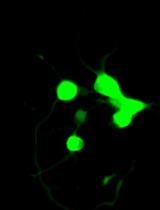

2. Preparation of samples for confocal microscopy: The microgels are prepared for analysis by confocal microscopy, which helps to visualize their structure and distribution.

• This protocol provides detailed instructions on the synthesis of fluorescently labeled emulsion microgels using mucoadhesive whey protein isolate, allowing the replication of this process.